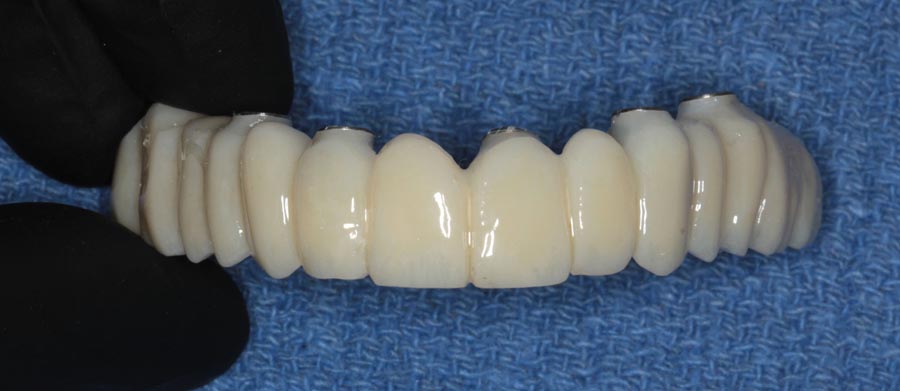

Smile GalleryImplant RestorationsFull Mouth Implant Restoration 1 of 13 Pre-operative smile Pre-operative smile Pre-operative frontal view, lips retracted Pre-operative panoramic image (note bone levels) Post-surgical panoramic image Surgical temporary bridge (note convex contours) Delivery of surgical temporary bridges in both upper and lower Two weeks post-op surgery and temporaries (note amazing tissue response) Three months post- surgery. (Note tissue development) Definitive implant bridges (FP-2) Post-treatment panoramic image Final result smile Final result smile